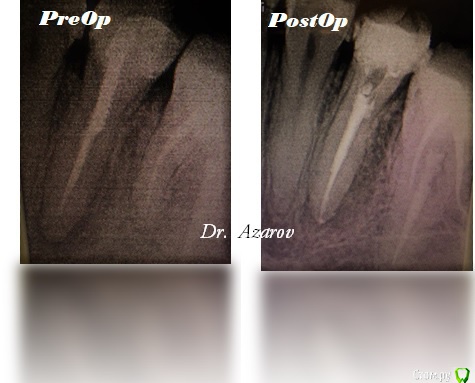

1586Doc Опубликовано 13 сентября, 2017 Поделиться Опубликовано 13 сентября, 2017 Идею оформления снимков честно подсмотрел у Каплана)) 1 Ссылка на комментарий